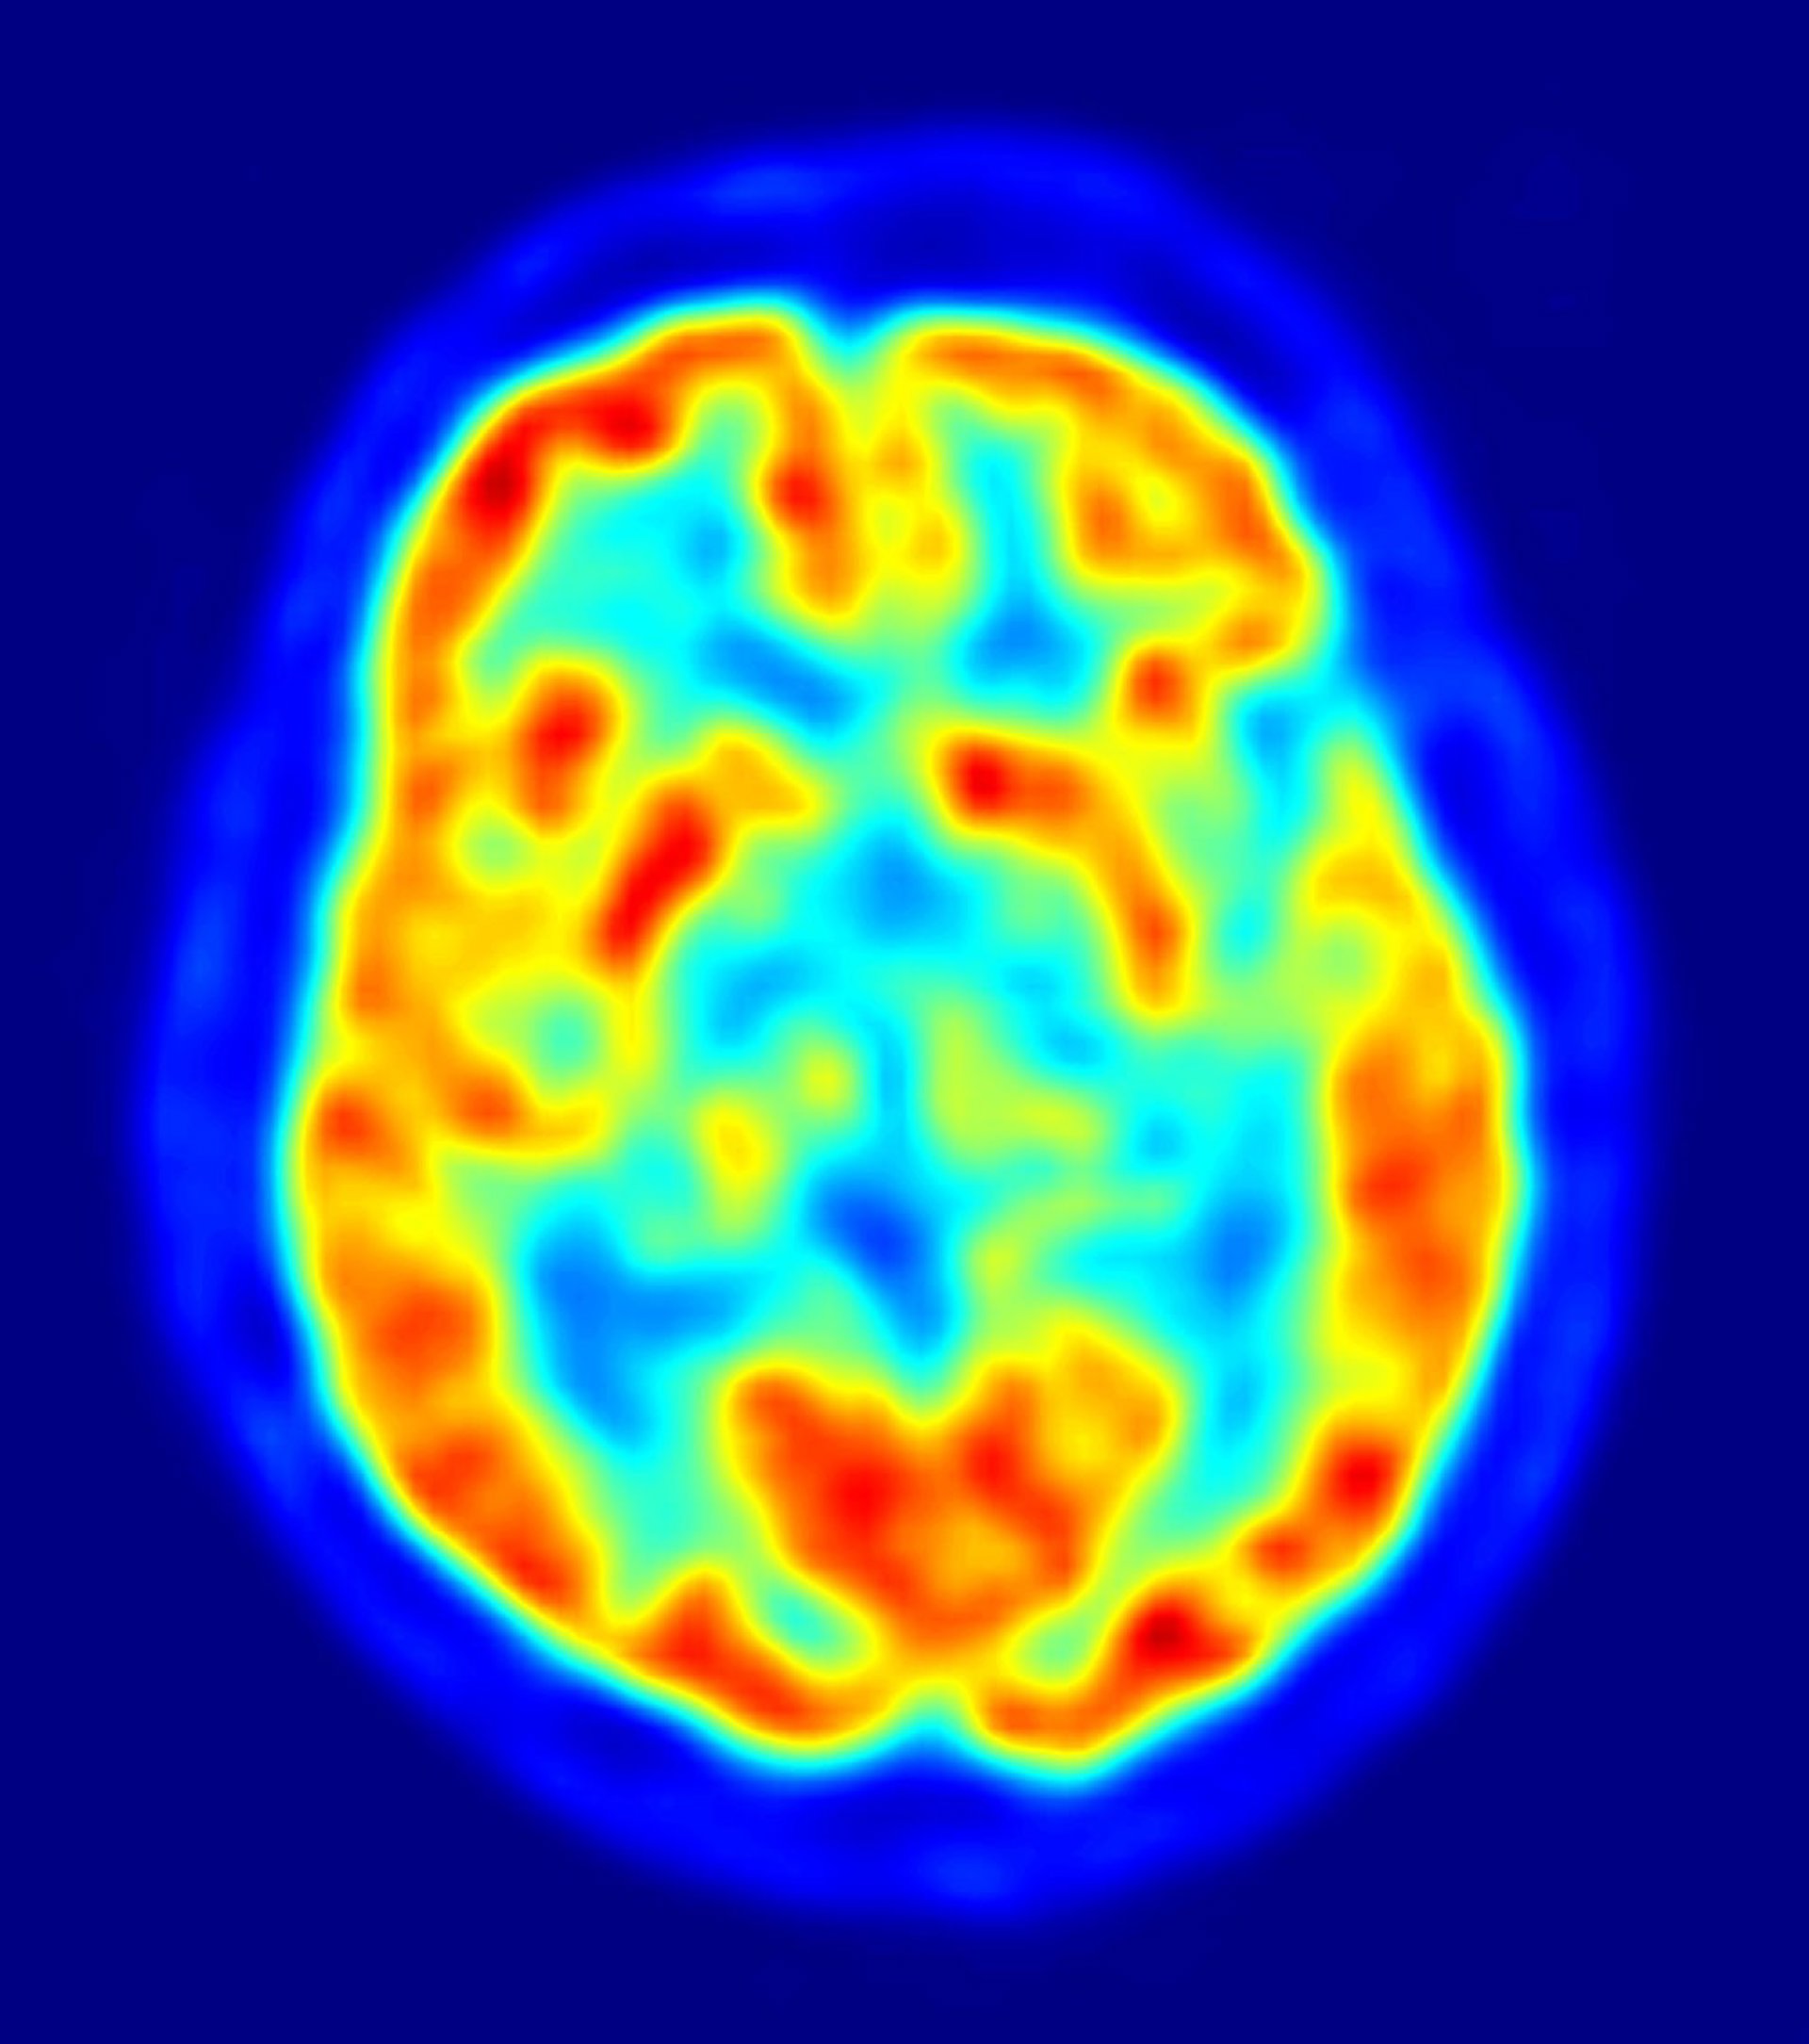

La reducción del espesor de ciertas áreas de la corteza cerebral es un indicador temprano del Alzheimer

Los pacientes con alto riesgo de padecer Alzheimer muestran una reducción del espesor de ciertas áreas de la corteza cerebral relacionadas con la memoria, en comparación con otras personas mayores sanas, según una de las principales conclusiones a las que ha llegado el equipo de investigación del Laboratorio de Neurociencia Funcional de la Universidad Pablo de Olavide (UPO), dirigido por el profesor José Luis Cantero Lorente.

Con este objetivo, sus investigaciones se centran en establecer un patrón de atrofias corticales, relativas a la corteza cerebral, y lesiones de la sustancia blanca cerebral --compuesta por fibras nerviosas, denominadas axones, que interfieren en la comunicación neuronal entre regiones cerebrales distantes-- que facilite un diagnóstico cada vez más temprano de la enfermedad.

Mediante técnicas de neuroimagen anatómica estos investigadores han observado lesiones de los tractos de fibras nerviosas que facilitan la liberación de acetilcolina en la corteza cerebral, un neurotransmisor implicado en diferentes funciones cognitivas como la consolidación de memoria, el lenguaje o la atención.

Asimismo, utilizan técnicas de resonancia magnética que les permiten determinar el grosor de la corteza cerebral, detectando un adelgazamiento de determinadas estructuras íntimamente relacionadas con la memoria (corteza entorrinal) en pacientes con deterioro cognitivo leve.